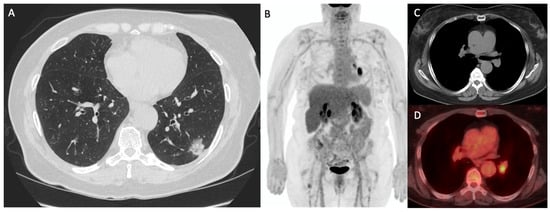

- Szyszko, T.A.; Yip, C.; Szlosarek, P.; Goh, V.; Cook, G.J. The role of new PET tracers for lung cancer. Lung Cancer 2016, 94, 7–14. [Google Scholar] [CrossRef] [PubMed]

- Wang, L.; Tang, G.; Hu, K.; Liu, X.; Zhou, W.; Li, H.; Huang, S.; Han, Y.; Chen, L.; Zhong, J.; et al. Comparison of 68Ga-FAPI and 18F-FDG PET/CT in the Evaluation of Advanced Lung Cancer. Radiology 2022, 303, 191–199. [Google Scholar] [CrossRef] [PubMed]

- Zhou, X.; Wang, S.; Xu, X.; Meng, X.; Zhang, H.; Zhang, A.; Song, Y.; Zhu, H.; Yang, Z.; Li, N. Higher accuracy of [68 Ga]Ga-DOTA-FAPI-04 PET/CT comparing with 2-[18F]FDG PET/CT in clinical staging of NSCLC. Eur. J. Nucl. Med. Mol. Imaging 2022, 49, 2983–2993. [Google Scholar] [CrossRef]

- Vesselle, H.; Grierson, J.; Muzi, M.; Pugsley, J.M.; Schmidt, R.A.; Rabinowitz, P.; Peterson, L.M.; Vallieres, E.; Wood, D.E. In vivo validation of 3’deoxy-3’-[18F]fluorothymidine ([18F]FLT) as a proliferation imaging tracer in humans: Correlation of [18F]FLT uptake by positron emission tomography with Ki-67 immunohistochemistry and flow cytometry in human lung tumors. Clin. Cancer Res. 2002, 8, 3315–3323. [Google Scholar] [PubMed]

- Muzi, M.; Vesselle, H.; Grierson, J.R.; Mankoff, D.A.; Schmidt, R.A.; Peterson, L.; Wells, J.M.; Krohn, K.A. Kinetic analysis of 3’-deoxy-3’-fluorothymidine PET studies: Validation studies in patients with lung cancer. J. Nucl. Med. 2005, 46, 274–282. [Google Scholar]

- Bading, J.R.; Shields, A.F. Imaging of cell proliferation: Status and prospects. J. Nucl. Med. 2008, 49 (Suppl. S2), 64S–80S. [Google Scholar] [CrossRef]

- Tian, J.; Yang, X.; Yu, L.; Chen, P.; Xin, J.; Ma, L.; Feng, H.; Tan, Y.; Zhao, Z.; Wu, W. A multicenter clinical trial on the diagnostic value of dual-tracer PET/CT in pulmonary lesions using 3’-deoxy-3’-18F-fluorothymidine and 18F-FDG. J. Nucl. Med. 2008, 49, 186–194. [Google Scholar] [CrossRef]

- Prekeges, J.L.; Rasey, J.S.; Grunbaum, Z.; Krohn, K.H. Reduction of fluoromisonidazole, a new imaging agent for hypoxia. Biochem. Pharmacol. 1991, 42, 2387–2395. [Google Scholar] [CrossRef]

- Huang, T.; Civelek, A.C.; Li, J.; Jiang, H.; Ng, C.K.; Postel, G.C.; Shen, B.; Li, X.F. Tumor microenvironment-dependent 18F-FDG, 18F-fluorothymidine, and 18F-misonidazole uptake: A pilot study in mouse models of human non-small cell lung cancer. J. Nucl. Med. 2012, 53, 1262–1268. [Google Scholar] [CrossRef] [PubMed]

- Thureau, S.; Chaumet-Riffaud, P.; Modzelewski, R.; Fernandez, P.; Tessonnier, L.; Vervueren, L.; Cachin, F.; Berriolo-Riedinger, A.; Olivier, P.; Kolesnikov-Gauthier, H.; et al. Interobserver agreement of qualitative analysis and tumor delineation of 18F-fluoromisonidazole and 3’-deoxy-3’-18F-fluorothymidine PET images in lung cancer. J. Nucl. Med. 2013, 54, 1543–1550. [Google Scholar] [CrossRef] [PubMed]